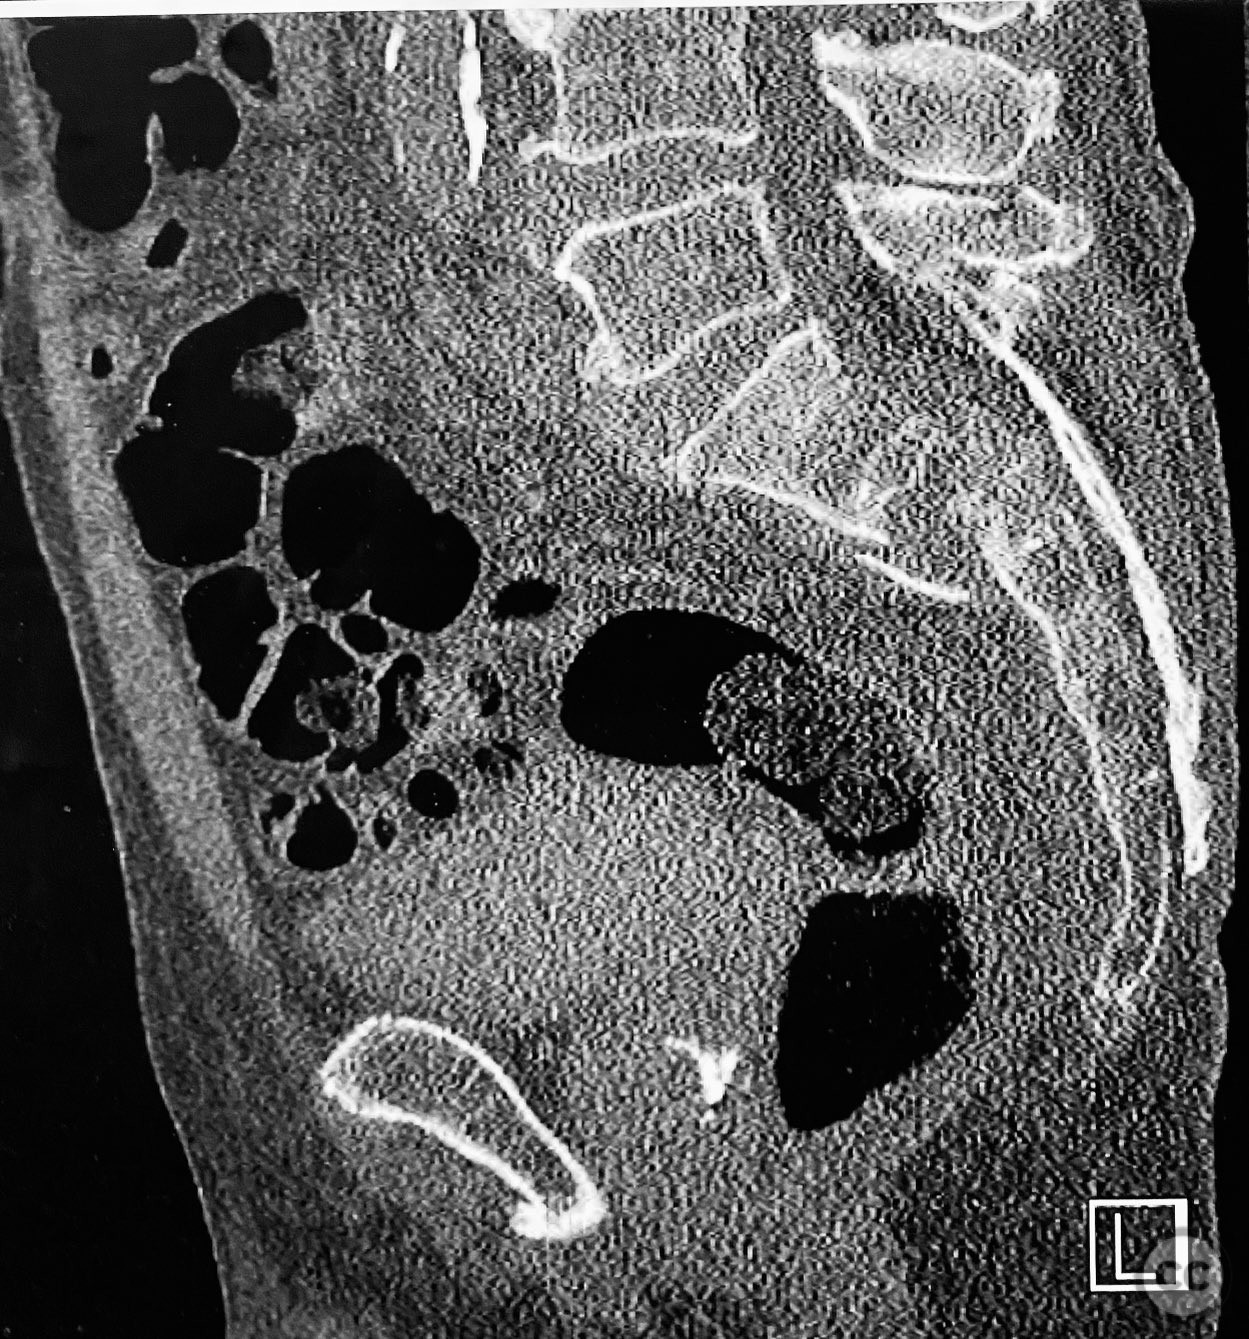

Pelvic Ring - AO/OTA 61x

Pelvis - AO/OTA 6x